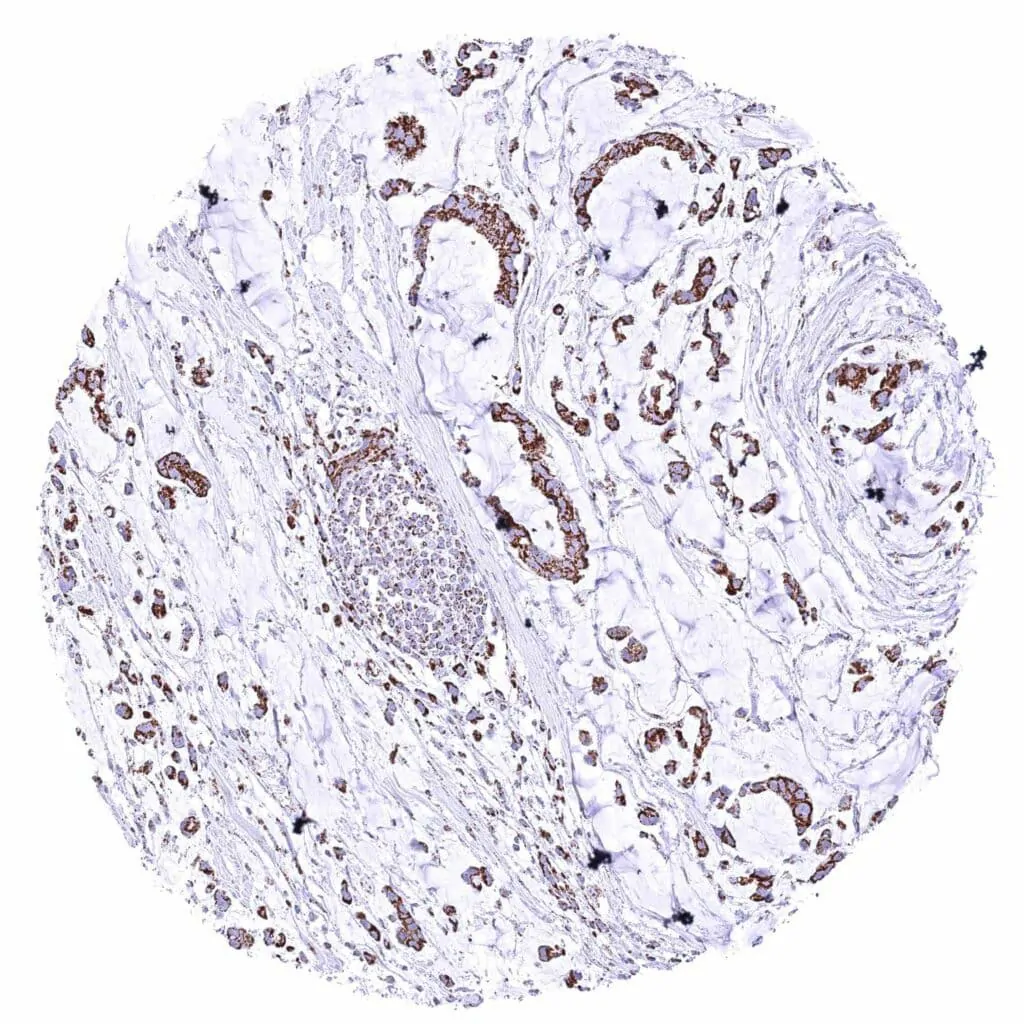

Pancreas – Ductal adenocarcinoma with weak cytoplasmic ATP5J immunostaining of tumor cells.